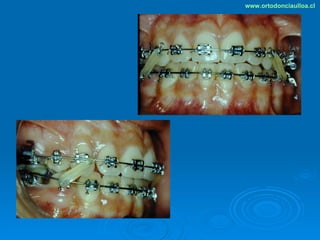

Este documento presenta dos casos clínicos de pacientes que recibieron tratamiento de ortodoncia. El primer caso fue de una paciente femenina de 14 años con apiñamiento dental y mordida cruzada que fue tratada mediante extracción de premolares y alineamiento dental. El segundo caso fue de un paciente masculino de 14 años con clase II esqueletal y desarmonía dentomaxilar que fue tratado con extracción de premolares y corrección de mordida. Ambos casos mostraron mejoría después de 3 años de tratamiento.